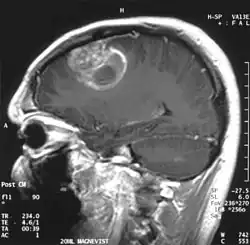

Sagittal MRI with contrast of a glioblastoma WHO grade 4 in a 15-year-old boy

When viewed with MRI, glioblastomas often appear as ring-enhancing lesions. The appearance is not specific, however, as other lesions such as abscess, metastasis, tumefactive multiple sclerosis, and other entities may have a similar appearance.[61] Definitive diagnosis of a suspected GBM on CT or MRI requires a stereotactic biopsy or a craniotomy with tumor resection and pathologic confirmation. Because the tumor grade is based upon the most malignant portion of the tumor, biopsy or subtotal tumor resection can result in undergrading of the lesion. Imaging of tumor blood flow using perfusion MRI and measuring tumor metabolite concentration with MR spectroscopy may add diagnostic value to standard MRI in select cases by showing increased relative cerebral blood volume and increased choline peak, respectively, but pathology remains the gold standard for diagnosis and molecular characterization.